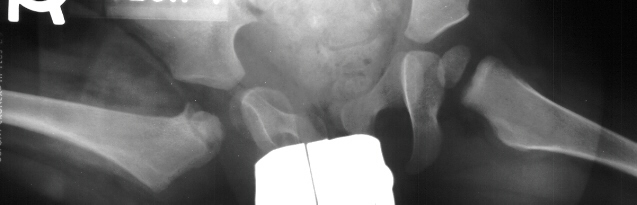

- Post Operative Day 18: R hip Xray: subluxation of R hip, possible metaphyseal

lucency consistent with osteomyelitis. Taken to OR for repeat I & D

of R hip via posterior approach with Penrose drains and hip spica cast

(15cc seropurulent fluid drained). Antibiotics changed to Oxacillin 225mg

IV q4.

- 2 month Office Follow Up: Rt hip Xray: progressive destruction of capital

femoral epiphysis, cystic changes in metaphysis consistent with AVN.

- Age 6: Valgus osteotomy for subluxation and 2cm leg length inequality.

- Age 15: Valgus osteotomy for hip incongruity.

- Age 20: Hip arthroscopy. Hip fusion recommended.

This case is an example of untreated septic arthritis which caused avascular

necrosis of the proximal femur. The primary cause of this is undrained

septic hip. Repeated aspiration is not adequect treatment of a septic hip.